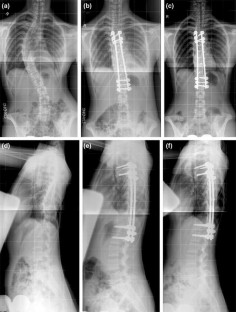

Fig. 2